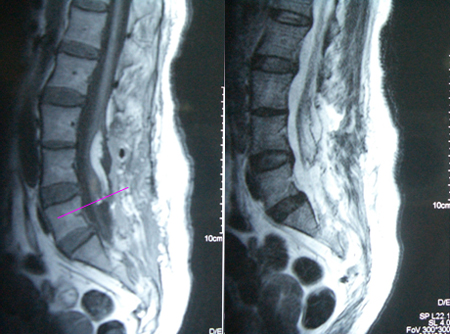

男性,43岁,无便意18年,右足麻木15年,加重延至双下肢3年。查体:步态稍显跛行,右侧L3~S5、左侧L4~S5针刺痛觉减退,双下肢深感觉障碍,双侧下肢远端肌力4级,双侧跟腱反射减弱,右侧肛门外括约肌松弛。术前影像学资料显示脊柱裂、椎管内脂肪瘤、脊髓拴系形成,有类神经结构向椎管外膨出。

手术在显微镜下进行,术中切除大部分脂肪瘤组织,切断终丝结构,术后影像学资料显示:脂肪瘤大部切除,脊髓圆锥上升约半个椎体节段。术后二便功能改善不明显,下肢肌力恢复,经进一步康复训练后二便功能有所改善。